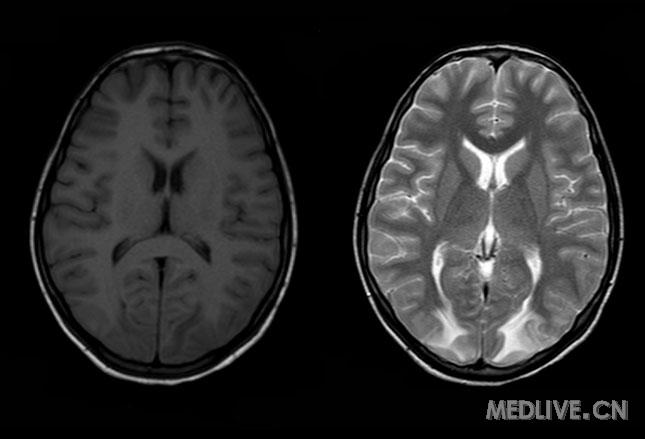

1多发性腔隙性脑梗塞多发性腔隙性脑梗塞多发性腔隙性脑梗塞多发性腔隙性脑梗塞((((脑白质病脑白质病脑白质病脑白质病))))腔隙性脑梗塞是在高血压腔隙性脑梗塞是在高血

脑白质病